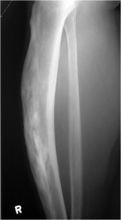

股骨側位片示左股骨皮質增厚,向前弓形變形X線

表現為受累骨的增粗和增厚,既有囊狀透光區又有骨硬化。骨皮質和松質界限消失,臂小梁粗大稀疏,密度不均,排列紊亂,呈條索狀高密度影交織,中間夾雜格線狀低密度區。早期以骨吸收為主,晚期以骨形成為主。沒有骨膜反應,也沒有軟組織腫塊。

長骨表現為增粗、彎曲,皮質骨變性增厚,病變與正常皮質骨分界處可見到“V”形分界線,可有病理骨折。在骨盆常出現髖臼內陷。病變在腰椎出現,則椎體明顯增大,骨小梁粗大,但椎間隙多保持正常。在顱骨表現為顱蓋骨異常增厚,離、低混雜密度,常伴有顱底凹陷,早期改變首先是外板破壞而內板仍保持完整。